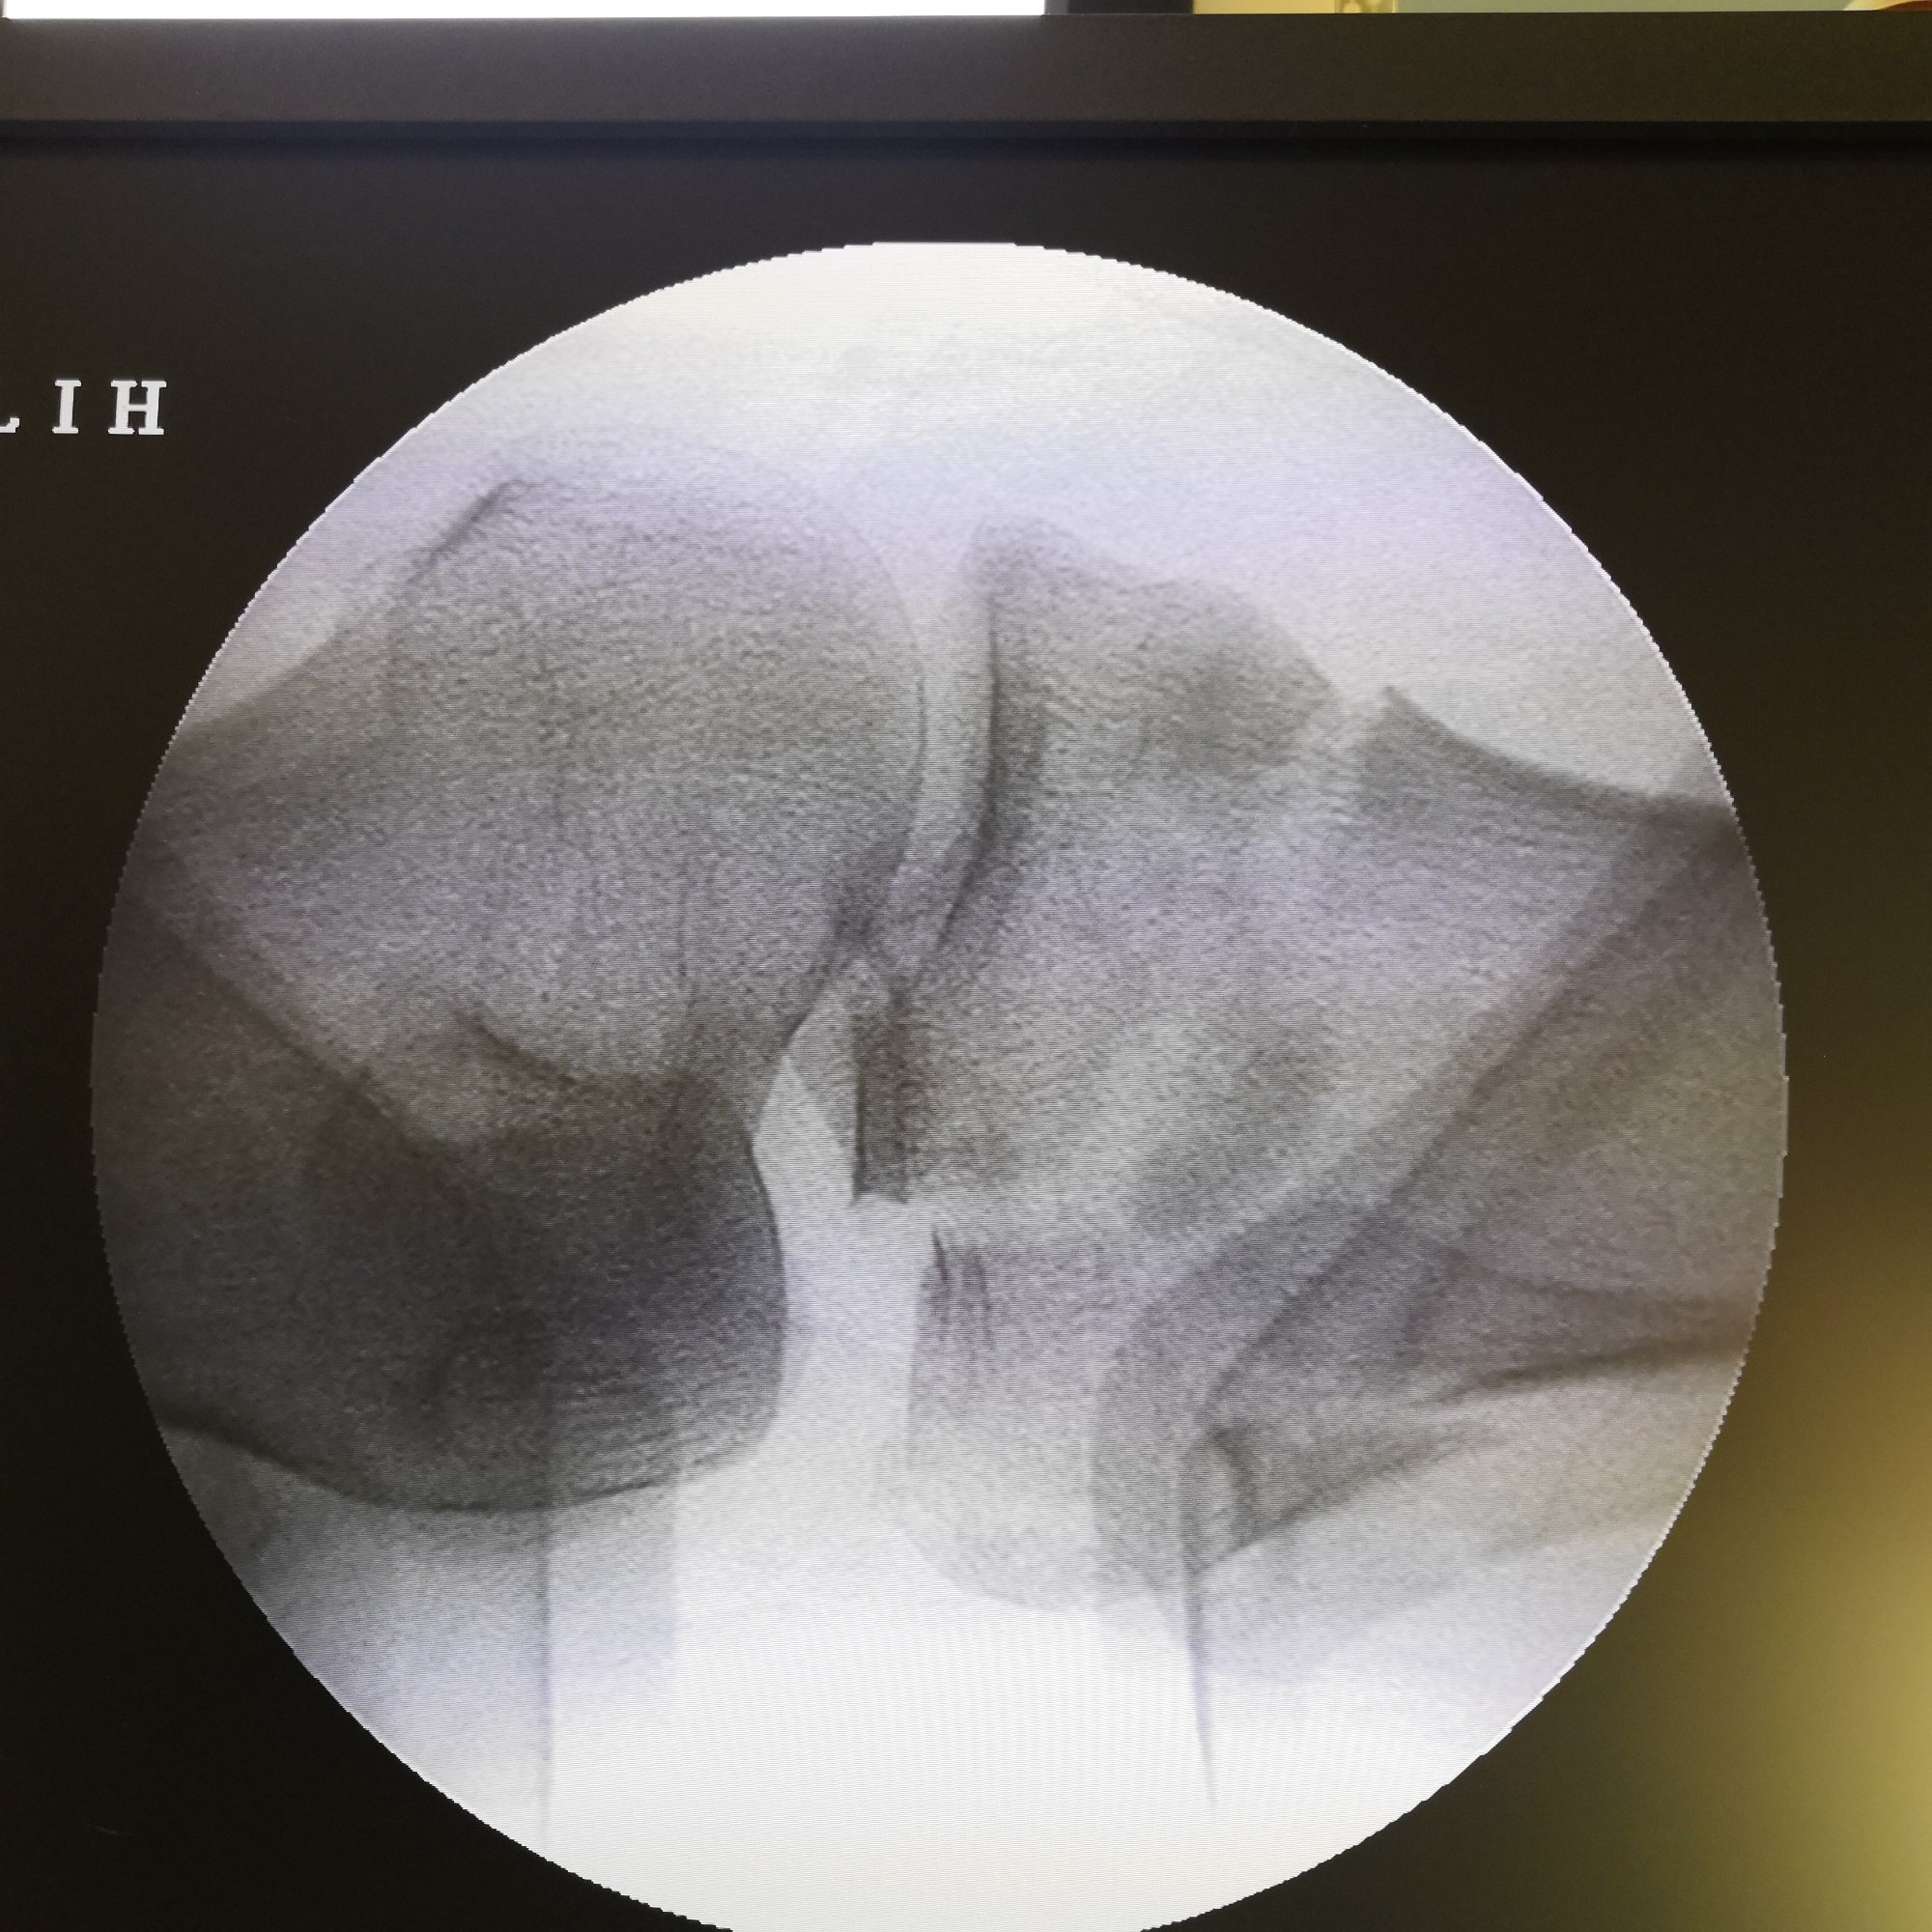

牵引复位前X光片